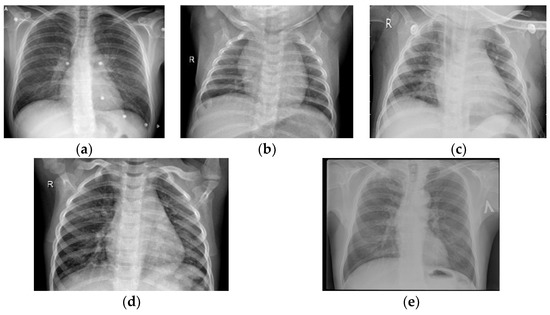

Secondly, before the combination of the two datasets, the redundant images for classification were filtered. For this reason, we eliminated the normal X-ray images in the second dataset while retaining those in the first dataset. The remaining images of these two datasets were integrated into a new dataset with five types of lung image features. The images in the new combined dataset were imaged in the same way and were all X-ray images. Various sample images in the new combined dataset are shown in Figure 2. The data distribution of each class is shown in Figure 3.

Figure 2. Sample display of each class: (a) COVID-19; (b) normal; (c) bacterial pneumonia; (d) viral pneumonia; (e) tuberculosis.